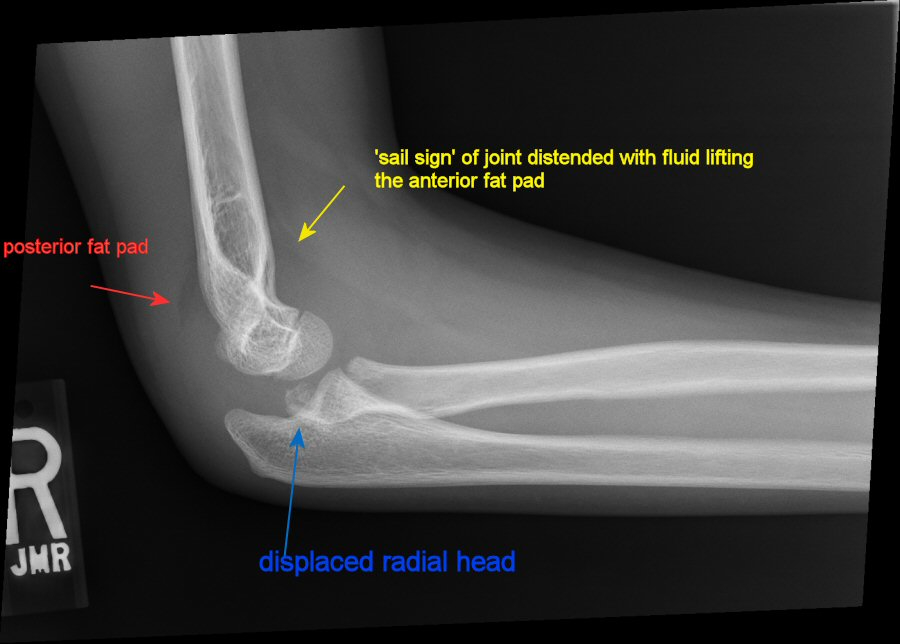

What is the most likely site of elbow fracture in pediatric patients?

Supracondylar

Unfortunately, they also tend to be hard to see on films. We often have to rely on elevation of the fat pads on plain films.

Where should you see a fat pad in a healthy elbow joint?